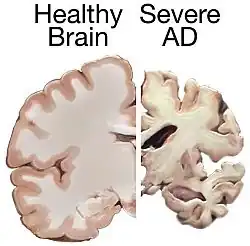

Alzheimer's disease

Alzheimer's disease is a common neurodegenerative disease and a form of dementia. It leaves patients impaired or unable to learn new information. They usually have difficulty coming up with the names of people, objects, etc. Degeneration or other neural problems because of this disease commonly occurs in parts of the Papez circuit. It is already known that problems with episodic memory are linked to tumors or damage in the Papez circuit. Specific structures of the Papez circuit linked to episodic memory are the hippocampus and other medial temporal lobe structures. As a result of these adverse effects on episodic memory, damage to the Papez circuit can not only indicate or predict amnesia but also Alzheimer's in a patient.[14]